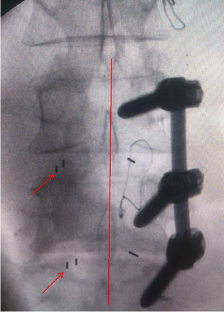

Fig. 1

Fig. 2

Fig. 3

Fig. 4

Fig. 5

Fig. 6

Fig. 7